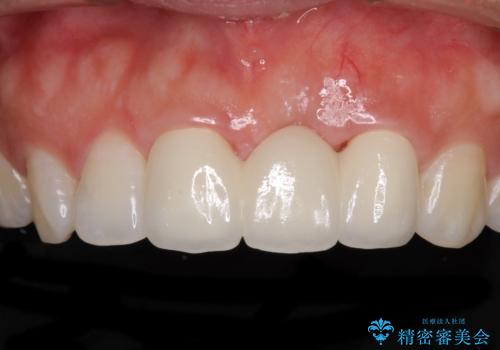

- 接着タイプの前歯のブリッジが不自然であるとのことで来院された患者様です。

欠損部の歯肉が窪んでいるため、歯肉移植により形態を改善し、オールセラミックブリッジにて補綴することとしました。

事前に装着されていた接着タイプのブリッジは、歯の切削量が少ない反面、接着界面から虫歯が進行しやすく、脱落リスクが高くなるというデメリットがあります。